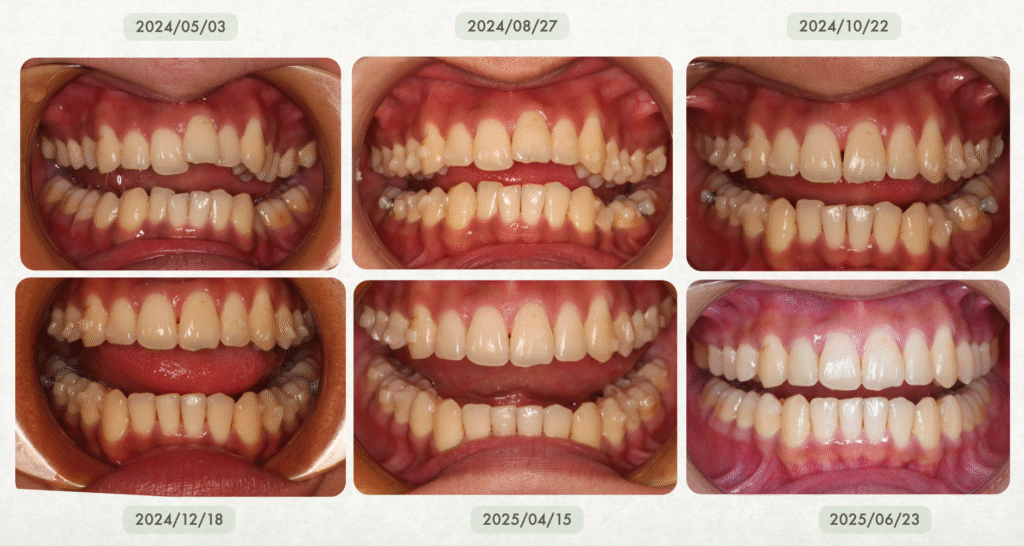

真實案例:隱適美有時甚至比傳統矯正還快!

在輕度到中度牙齒凌亂的案例中,隱適美不但不慢,反而更有效率、更快完成。

- 若配戴配合度良好,療程甚至可能在一年內順利完成

很多人驚訝地發現:「原來隱適美也可以這麼快!」

在 沐森美學牙醫 的實際經驗中,隱適美治療並不會特別久,甚至在某些案例中,反而可以比傳統矯正更有效率、完成得更快✨!

尤其在輕度到中等牙齒凌亂的情況下,隱適美有非常大的機會比傳統矯正更快速完成喔~而且費用也跟傳統矯正差不多!